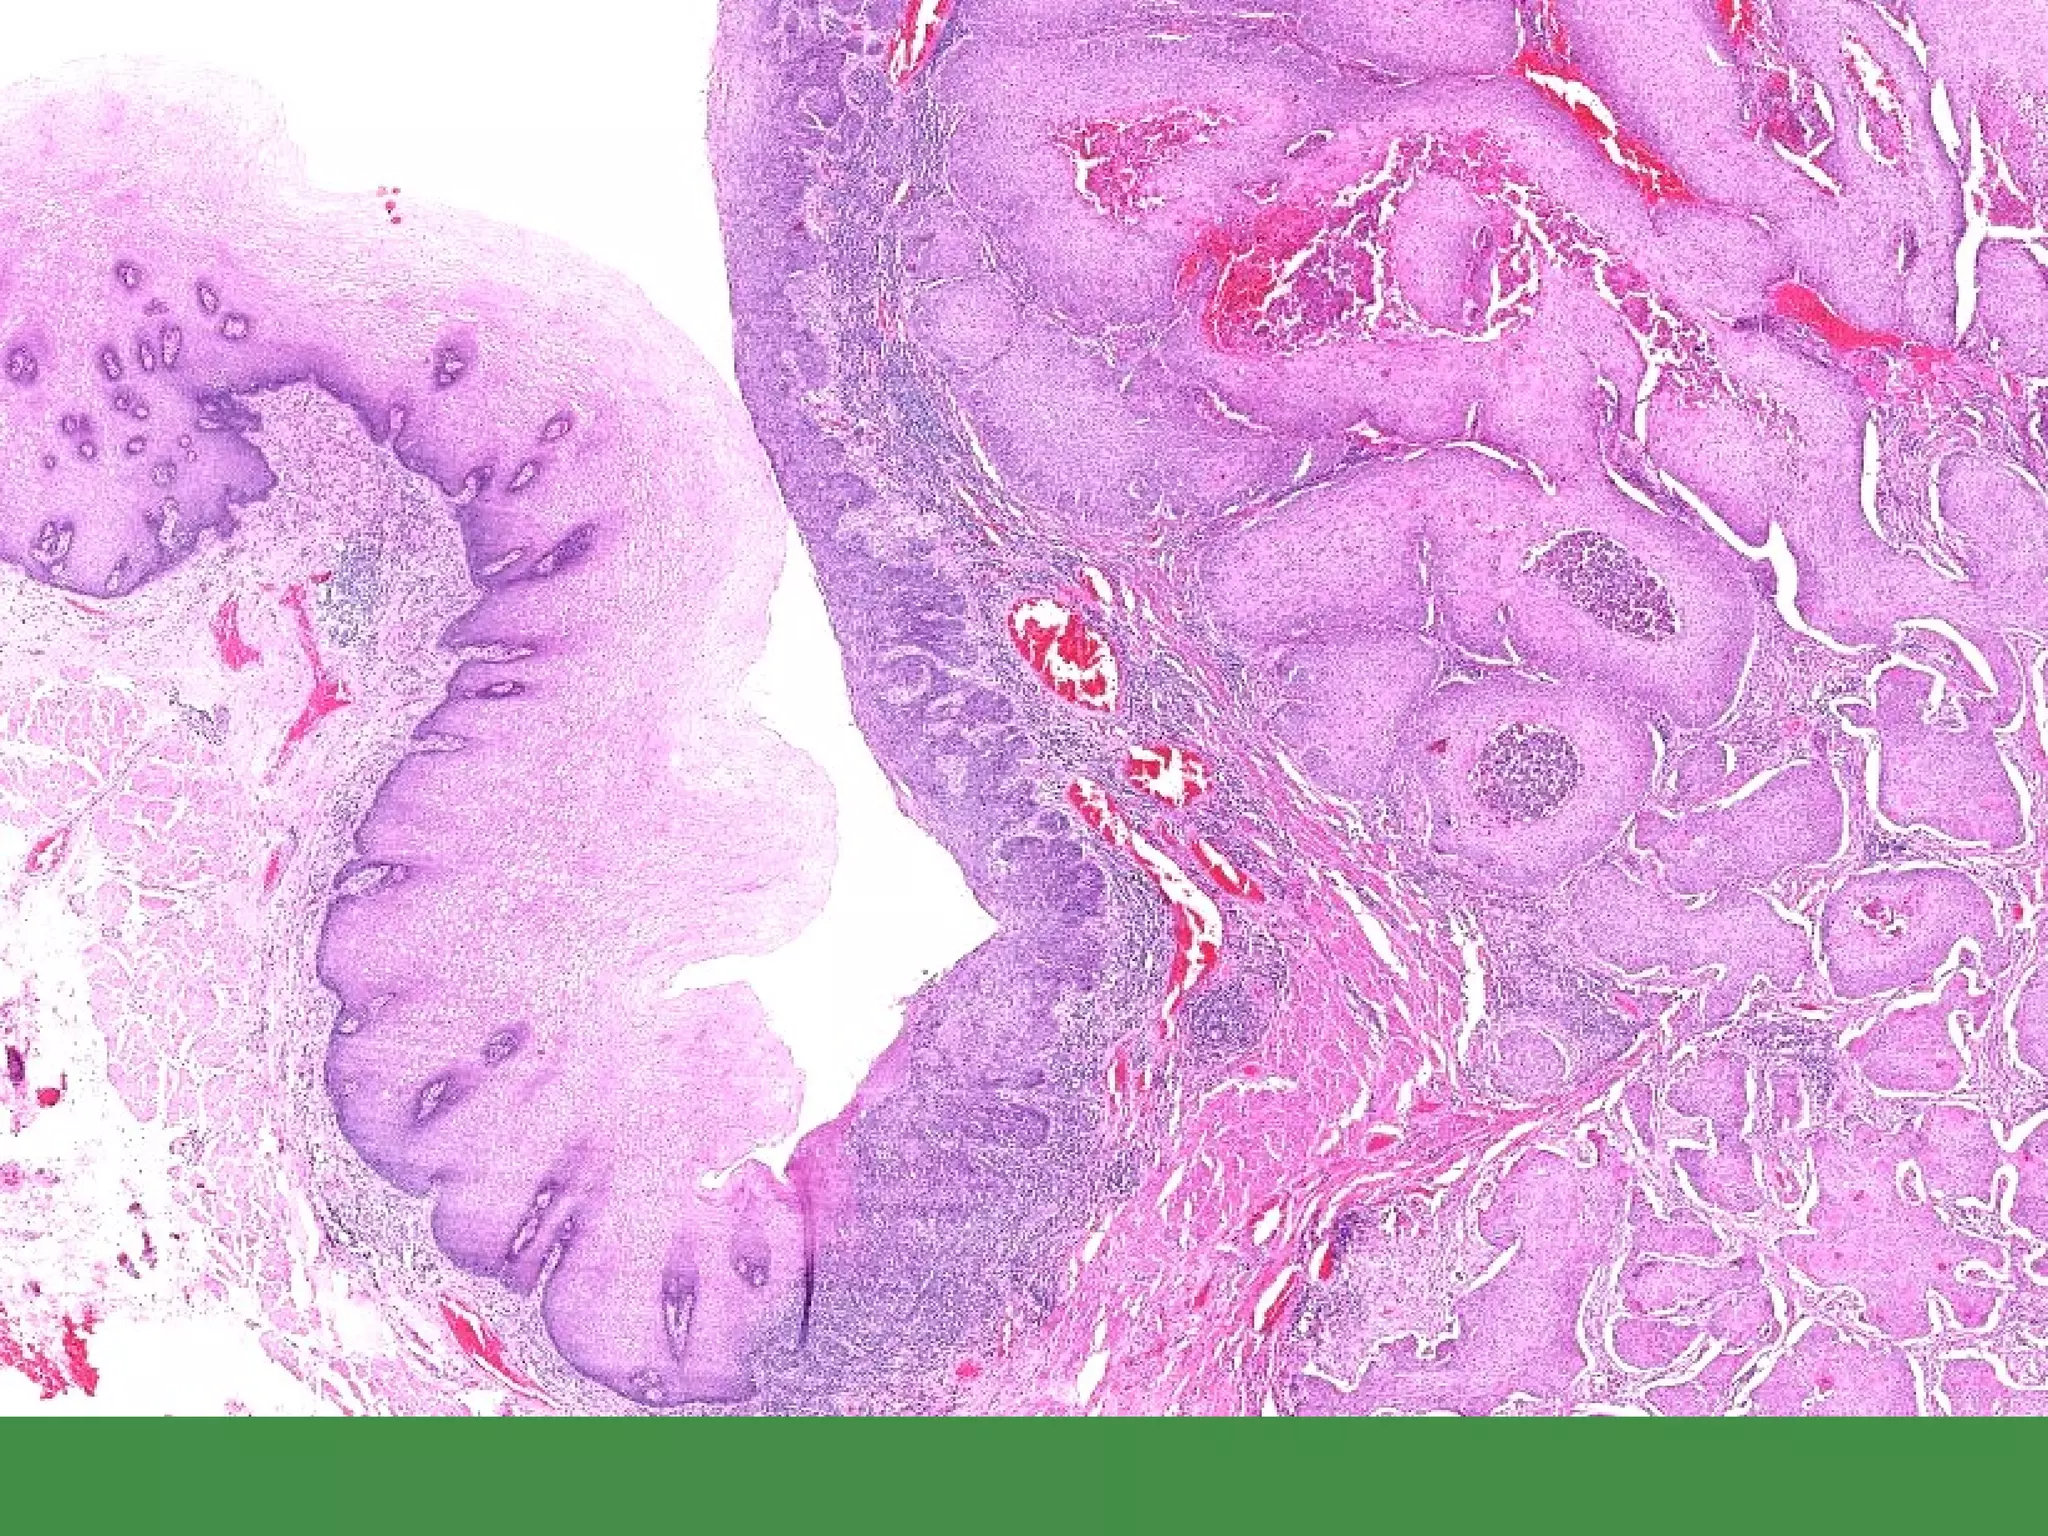

POLYPS ANY mucosal bulging, blebbing, or bump HYPERPLASTIC  (NON-NEOPLASTIC) HAMARTOMATOUS  (NON-NEOPLASTIC) ADENOMATOUS  (TRUE NEOPLASM, and regarded by many as PRE-MALIGNANT as well) SESSILE vs. PEDUNCULATED TUBULAR vs. VILLOUS

POLYPS ANY mucosalbulging, blebbing, or bump HYPERPLASTIC (NON-NEOPLASTIC) HAMARTOMATOUS (NON-NEOPLASTIC) ADENOMATOUS (TRUE NEOPLASM, and regarded by many as PRE-MALIGNANT as well) SESSILE vs. PEDUNCULATED TUBULAR vs. VILLOUS

• #30 Glandular “dysplasia”

• #156 NOTE the various types of epithelial cells….this is the reason it is benign, i.e., NON monoclonal.

• #157 TUBULAR adenoma, note how all the epithelial (glandular) cells look the same.

• #158 Villous adenomas behave more aggressively than tubular adenomas